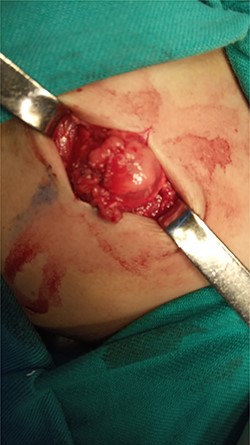

After studying the case, we decided to perform primary repair of the abdominal wall defect without meshplasty since the diameter of the aperture was <5 cm. An oblique left lumbar incision was performed above the hernia, revealing a defect measuring 4 cm in diameter in the upper lumbar triangle. Dissection of the peritoneum and hernial sac was performed starting from the margins of abdominal muscles (Fig. 4), the hernial sac was internally reduced and the muscular margins were closed by simple continuous sutures made from prolene 0 (Fig. 5). Complete closure of the defect was confirmed and a draining tube was inserted subcutaneously before closing the skin. The drain was removed after 2 days; the stitches were removed after 10 days. The patient was faring well after the surgery. Recurrence of the hernia was not reported. We recommended that the patient should be followed up by an orthopedist for the correction of disability, which is caused by LCVS.